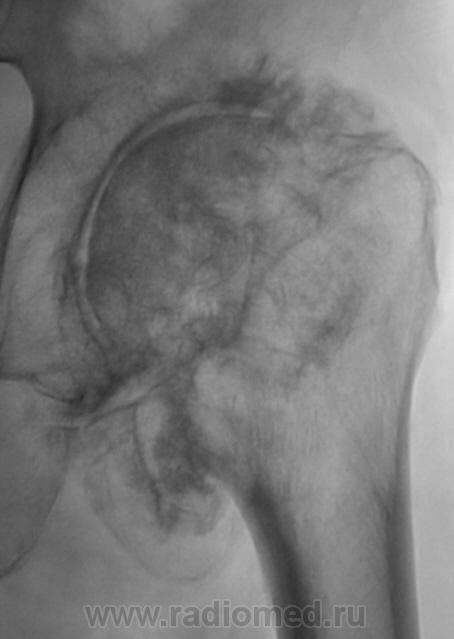

И вторичные выраженные деформирующие изменения на фоне двусторонней дисплазии суставов. Хондроматоз суставов

Наверное, в основе дисплазия (никогда такой не видел), но и об остеоартропатии мысль есть. Предполагаю заболевание спинного мозга.

Пациент в течение 3 лет самостоятельно не передвигается, основное положение - лежа.

сирингомиелия?

Наиболее вероятен диспластический генез коксартроза.

Последствия болезни Пертеса?